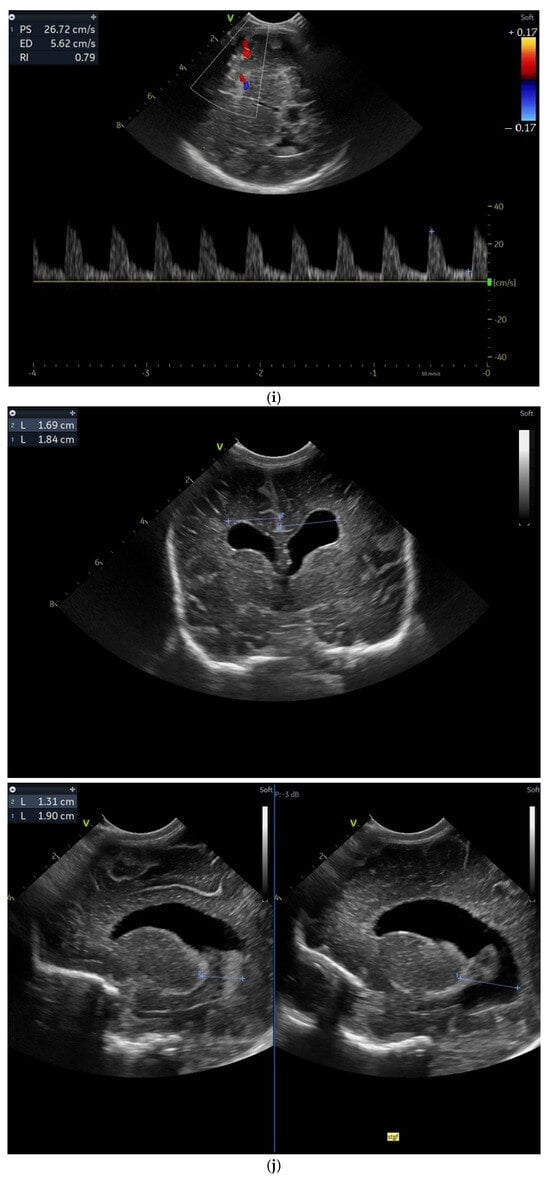

Case 5 involved a 35-week gestational age newborn who presented with birth asphyxia and required resuscitation after delivery, which involved a balloon and mask and then a balloon and laryngeal mask, and afterwards mechanical ventilation in the NICU (Neonatal Intensive Care Unit) with SIMV/IPPV (synchronized intermittent mandatory ventilation/invasive positive pressure ventilation), who was antenatally diagnosed through MRI with subacute polyhydramnios and ventriculomegaly due to a suspected medulla oblongata tumor (Figure 5a).

Figure 5.

(a,b) MRI—T2 sequence. Sagittal view. Antenatal. Yellow arrows indicate the place of the suspected tumor (personal image collection). (c) Cranial ultrasound. Sagittal view. Up—enlarged left ventricle. D1—thamalo-occipital distance. Down—enlarged right ventricle. D1—thalamo-occipital distance (personal image collection). (d) Cranial ultrasound. Sagittal view. Enlarged third ventricle. Fourth ventricle is normal. D1, D2—measurements of the third ventricle (personal image collection). (e) Cranial ultrasound. Transtemporal view. Enlarged third ventricle. Sylvian aqueduct is not visible. D1—measurement of third ventricle. LV AH—lateral ventricle anterior horn. LV OH—lateral ventricle occipital horn. V 3—third ventricle (personal image collection).

After stabilization, the cranial ultrasound exam revealed enlargement of the lateral ventricles and third ventricle, with a normal fourth ventricle. There was no visualization of the Sylvian aqueduct, which raised the suspicion of aqueduct atresia or stenosis (Figure 5c–e). There was no improvement seen in the cranial ultrasound examinations that followed.

The aEEG pattern was initially a discontinuous normal voltage, which was normal for the newborn’s gestational age. At 12 h of life, there were short episodes of electrical seizures with no clinical manifestations. The seizures ceased after the administration of Phenobarbital but the pattern changed to burst suppression for approximately an hour and then returned to a discontinuous normal voltage with rudimentary sleep–wake cycles. Due to the absence of seizures, the aEEG was stopped after 48 h.

Unfortunately, the general condition of the newborn was very unstable, which was the reason why the patient was transferred to the Maria Sklodowska Curie Hospital for Children, Bucharest, for further investigations and treatment.